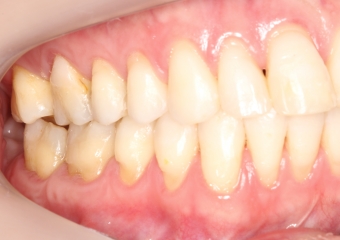

Mordida inicial